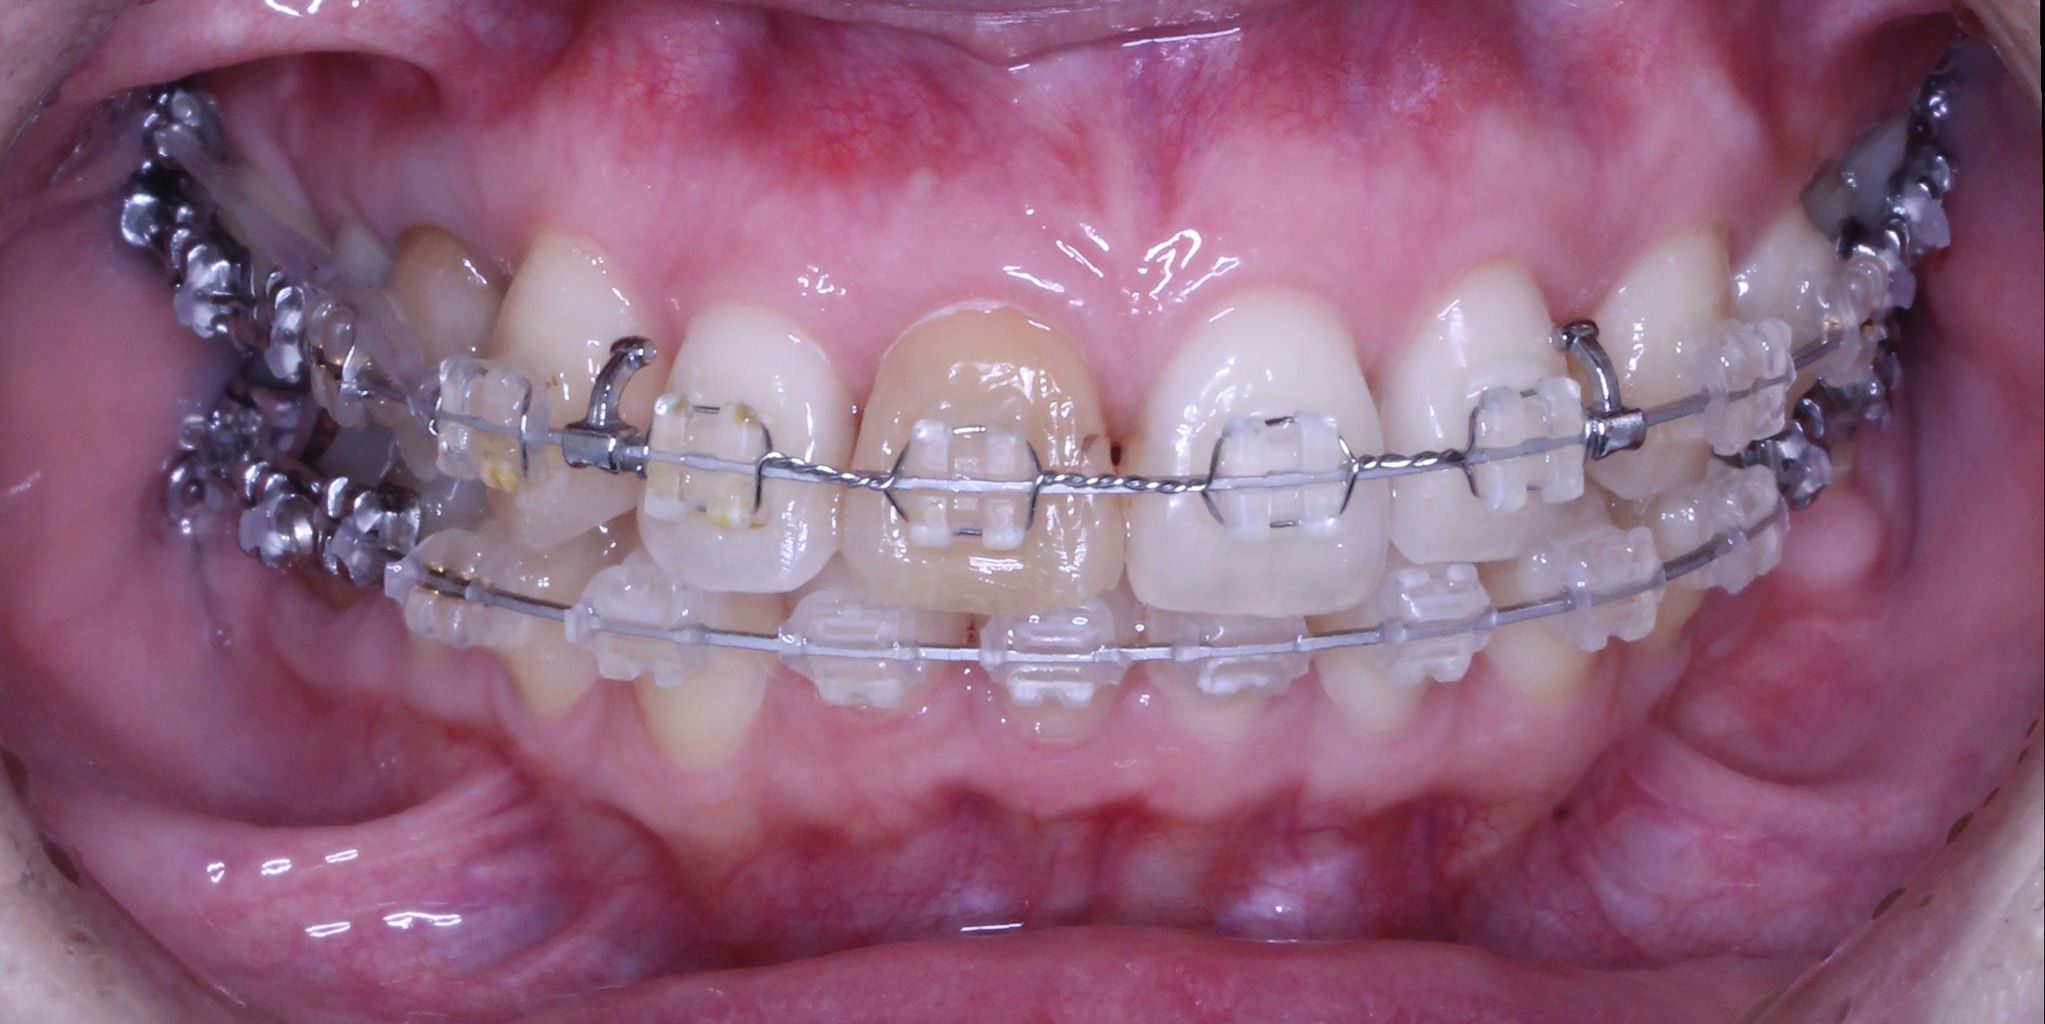

それでは本日の症例です

虫歯治療はきちんとされてますが、奥歯に全部銀歯の状態の歯があります。

当然、神経もない歯です。治療されたのはだいぶ前とのことでした。

患者さんの主訴は口元をひっこめたいでした。

そうなると抜歯しての歯列矯正治療は必須です。また、口元の改善を考えると、前歯よりの歯を抜歯したほうが治療的には容易です。

しかしながら、いつ治療したか記憶にない銀歯があります。神経もとってしまってますし、中がどのような状態になっているか把握できません。治療中に歯がとれてしまい、結果的に抜歯となってしまう可能性もございます。

それでは治療経過です

少し経過が進みました

治療開始から3年経過した現在の状況です